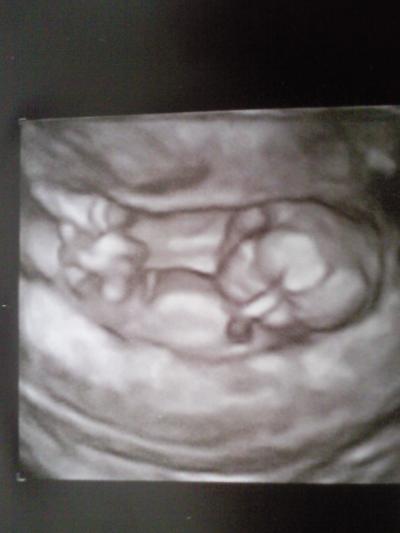

Hallo Ihr Lieben, war seit Freitag im Krankenhaus und bin heute Morgen glücklicherweise entlassen worden. War schon Freitag Vormittag wegen Blutung beim FA- der hat mich jedoch mit der Bestätigung das alles okay is wieder nachhause geschickt. Am Nachmittag bin ich dann wegen stärkeren Blutungen und Schmerzen ins Krankenhaus. Dort wurde ein Blasensprung festgestellt. Glücklicher Weise bei der 2. leeren Fruchthülle und nicht bei meinen kleinen Zwerg. Damit keine Infektion entsteht musste ich einige Tage mit Antibiotika behandelt werden. Dem Zwerg geht es nach gestrigerm US super und er is auch zeitgerecht mit 5.6 cm super für 13+3 SSW entwickelt. Hoffe jetzt das das der letzte Zwischenfall dieser Art war, jedoch habe ich immernoch ein riesiges Hämatom und leichte Blutungen. Aber morgen habe ich nochmal eine US Untersuchung und reguläre Vorsorge - dann wird nochmal besprochen welche Vorsichtsmaßnahmen ich treffen kann um den Zwerg bestens zu schützen. Hier noch ne Bildchen von gestern.

Bild zu Mich mal zurückmelden möchte - Forum für November - Mamis